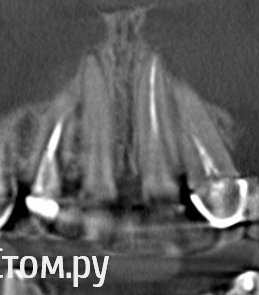

stradalitca Опубликовано 20 мая, 2014 Поделиться Опубликовано 20 мая, 2014 Здравствуйте! у меня такая проблема. Примерно 23 декабря мне сразу пролечили каналы и поставили пломбы световые на два центральных верхних. Помню, что именно в правый зуб в конце, по ощущениям, врач что-то вонзила в канал, что я вздрогнула - как будто аж насквозь зуб и дальше. В тотже день появилась небольшая тупая боль при нажатии в районе верхушки корня( около правой ноздри).Ну и если скажем сгримасничать и губой провести по "фасаду" правого центрального. Через пару месяцев я всё же решила сходить к врачу. Сразу предварительно сделала рентген- правый оказался с не до конца пролеченным каналом( лишь примерно на 70%). врач перепломбировала канал. Но вот уже прошло ещё три месяца, а боль так и осталась.В принципе она меня не особо беспокоит. Но беспокоит вопрос - а не грозит ли мне это какими-то последствиями?. 12 мая сама пошла и сделала 3D зубов. Вот что получилось. Может подскажете, что не так с правым зубом? Ссылка на комментарий

Korel Опубликовано 27 мая, 2014 Поделиться Опубликовано 27 мая, 2014 Похоже на перфорацию отмеч. зелён. стрелочкой. http://s020.radikal.ru/i721/1405/40/d7e4ef25a75e.jpg Ссылка на комментарий

sydnik Опубликовано 27 мая, 2014 Поделиться Опубликовано 27 мая, 2014 очень похоже на перфорацию Ссылка на комментарий

stradalitca Опубликовано 1 июня, 2014 Автор Поделиться Опубликовано 1 июня, 2014 в начале темы я раместила три фото. на одном, в коричневых тонах, этот зуб( 11) на корне какой-то не такой. в смысле верхушке зуба. Пожалуй, меня это единственное, что смущает. Ссылка на комментарий

Korel Опубликовано 1 июня, 2014 Поделиться Опубликовано 1 июня, 2014 Уважаемые стоматологи, кто-нибудь смотрел последние мои снимки? ( те, где вроде как двойка проглядывает, а не перфорация)? Склоняюсь к перфо. в начале темы я раместила три фото. на одном, в коричневых тонах, этот зуб( 11) на корне какой-то не такой. в смысле верхушке зуба. Пожалуй, меня это единственное, что смущает. Аналогично. я никого не хотела обидеть. И тем более Мону. Мона не обидчивая)) Ссылка на комментарий